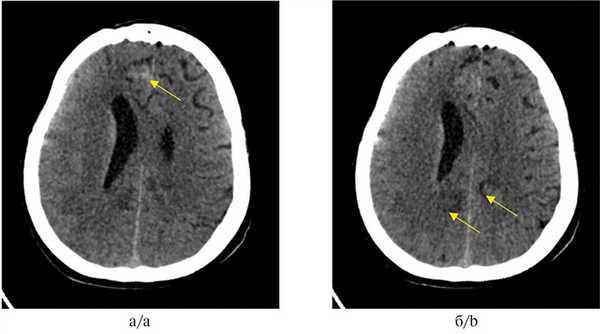

Рис. 1. МСКТ головного мозга.

а — опухолевый очаг в правой лобной доле, указан стрелкой; б — опухолевые очаги в левой и правой затылочных долях, указаны стрелками.